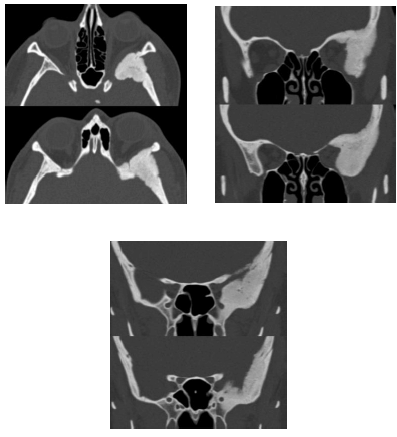

Paciente com 44 anos de idade, do sexo feminino, apresenta exoftalmia à esquerda de causa desconhecida, sem outras queixas ou outras patologias conhecidas. A seguir são mostradas imagens obtidas pela tomografia computadorizada realizada pela paciente.

Além da modalidade esclerótica, essa lesão pode ainda apresentar aspecto em vidro fosco, cístico, ou em “bolhas de sabão”.

A cintilografia óssea não demonstrará captação nas áreas afetadas pela doença, de modo que não auxiliaria na avaliação da sua distribuição e atividade, embora colaborasse no diagnóstico diferencial com doença de Paget.

A referida lesão determina densificação e importante aumento de resistência do osso acometido, além de comumente expandir o osso comprimindo às estruturas adjacentes, sem, contudo, invadi-las.

A forma poliostótica dessa doença, em associação com lesões cutâneas tipo “café-com-leite” e puberdade precoce, sugeriria a possibilidade de síndrome de Von Recklinghausen.

O quadro é típico de displasia fibrosa esclerótica, havendo a possibilidade de meningioma em placa como importante diagnóstico diferencial.